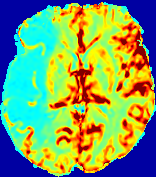

LesionRefer to captionRefer to captionRefer to captionRefer to captionRefer to captionRefer to caption𝐕rgbsubscript𝐕𝑟𝑔𝑏{\bf{V}}_{rgb}Refer to captionRefer to captionRefer to captionRefer to captionRefer to captionRefer to caption𝐕2subscriptnorm𝐕2{\|\bf{V}}\|_{2}Refer to captionRefer to captionRefer to captionRefer to captionRefer to captionRefer to captionRefer to caption3.53.53.52.82.82.82.12.12.11.41.41.40.70.70.70.00.00.0(mm/s)𝑚𝑚𝑠(mm/s)D𝐷DRefer to captionRefer to captionRefer to captionRefer to captionRefer to captionRefer to captionRefer to caption0.0200.0200.0200.0160.0160.0160.0120.0120.0120.0080.0080.0080.0040.0040.0040.0000.0000.000(mm2/s)𝑚superscript𝑚2𝑠(mm^{2}/s)Slice #1Slice #2Slice #3Slice #4Slice #5Slice #6

Figure 3: PIANO feature maps for one stroke patient, where the lesion is located in the left hemisphere. Top row: segmented stroke lesion region (white) on different slices, obtained from ISLES 2017. The corresponding slices for the PIANO feature maps are shown in the following rows.

For a better insight into an estimated velocity field 𝐕𝐕{\bf{V}} and diffusion field 𝐃𝐃{\bf{D}}, we compute the following maps: (1) 𝐕rgbsubscript𝐕𝑟𝑔𝑏{\bf{V}}_{rgb}: Color-coded orientation map of 𝐕=(Vx,Vy,Vz)T𝐕superscriptsuperscript𝑉𝑥superscript𝑉𝑦superscript𝑉𝑧𝑇{\bf{V}}=(V^{x},V^{y},V^{z})^{T}, obtained by normalizing 𝐕𝐕{\bf{V}} to unit length and mapping its 3 components to red, green, blue respectively; (2) 𝐕2subscriptnorm𝐕2\|{\bf{V}}\|_{2}: 222 norm of 𝐕𝐕{\bf{V}}; (3) D𝐷D: scalar field in Eq. 5.

Fig. 3 and Fig. 4 show the PIANO feature maps estimated from two ISLES 2017 patients: all are highly consistent with the lesion in both cases. Details of the blood flow trajectories are revealed in 𝐕rgbsubscript𝐕𝑟𝑔𝑏{\bf{V}}_{rgb} by the ridged patterns and the sharp changes of colors in the unaffected (right) hemisphere, while the flat patterns appearing within the lesion provide little directional information about the velocity and indicate low velocity magnitudes. Velocity magnitudes are more directly visualized via 𝐕2subscriptnorm𝐕2\|{\bf{V}}\|_{2}, from which one can easily locate the lesion where 𝐕2subscriptnorm𝐕2\|{\bf{V}}\|_{2} is low. D𝐷D also indicates lower diffusion values in the lesion, though with less contrast potentially due to the fact that it captures the accumulated effect of CA diffusion at the voxel-level.